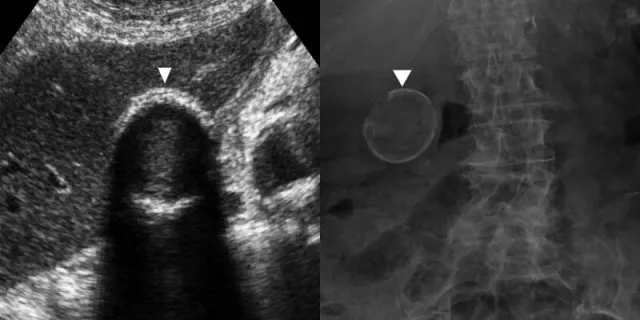

- Diagnosis: Ultrasound (initial), CECT Abdomen (staging), MRCP/ERCP (biliary assessment). CA 19-9 (tumor marker).

⭐ Porcelain gallbladder, a premalignant condition, necessitates prophylactic cholecystectomy due to high cancer risk (up to 25%).